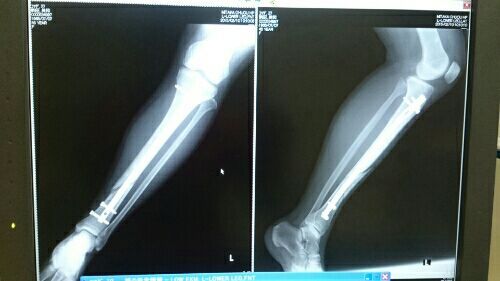

2016bone01.jpg

2015年1月12日の骨折から3日目の入院初日

2016bone02.jpg

手術から3日目。まだ足がパンパンです。

包帯の下は全体が内出血となって、7日程は常にアイシング状態でした。

そして下が、術後1ヶ月でのレントゲン。

2016bone03.jpg

1年に10回位のレントゲンをとって被爆の心配も少々感じつつも

2015年12月の診察で、骨折の隙間は依然見られるものの

転ばないことを誓ってスキーの許可をもらい、

2016年2月29日の診察でここまで来たら、金属は抜いてもOKです。

くっついたとしましょう、ということで4月の手術となりました。

抜糸の日にとったレントゲンでは金属が入っていた箇所は全てキレイに

画像に写っていました。

ボルト部分を含めて2ヶ月~4ヶ月で埋まるらしく、密度の濃さの違いで

レントゲンには4、5年は映り込むらしいですが動きに制限はないとのことです。